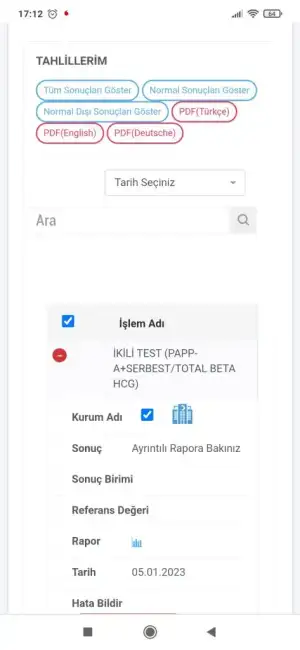

Ben ikili test yaptirmadim